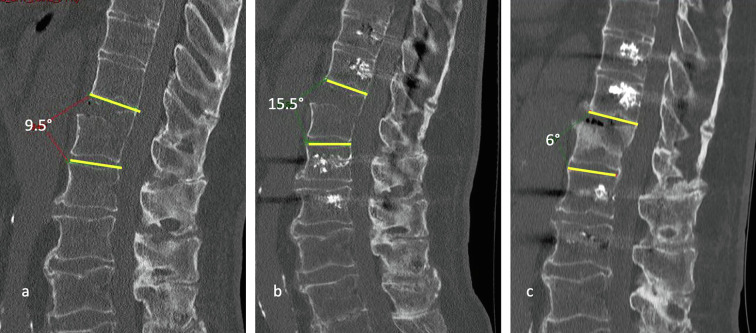

Methods: This retrospective study included 46 patients, mean age 79.3 years, with ASD, who underwent isolated posterior stabilization, open or percutaneous, for thoracolumbar fractures. The average follow-up was 21.7 months, with a minimum follow-up of 6 months. Autonomy (Parker score) and radiological results (lordotic angulation) were analyzed pre-and post-operatively.

Results: Autonomy was maintained at the last follow-up, with no significant difference in Parker's score. The consolidation rate was 94.6%. No implant failure was recorded. Despite the absence of an anterior procedure, lordotic angulation was significantly reduced by 2.6° at 6 months (p = 0.02). The rate of surgical complications following open surgeries was 10.9% (n = 5), of which 6.5% were infections. No surgical complications were reported in percutaneous surgeries. The rate of medical complications was 67.4% (n = 31), with a rate of 88.2% in the open surgery group, compared to 55.2% in the percutaneous surgery group. An open approach was associated with a five-fold higher risk of complications (p = 0.049). Nine patients died during follow-up (19.6%).